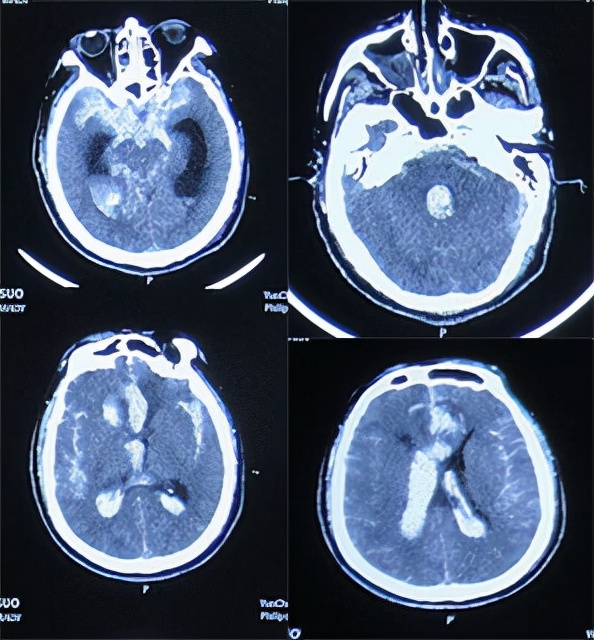

患者2020年10月16日6时30分晨起突发头晕呕吐,伴有意识不清,家属拨打120,将其送入山西省运城市某医院,急诊查头部CT示额叶脑出血伴广泛蛛网膜下腔出血、脑室内铸型( 图-1 );住入重症病房。

图-1: 2020年10月16日头部CT:额叶脑出血伴广泛蛛网膜下腔出血、脑室内铸型

住院次日即2020年10月17日3点行全脑血管造影术示前交通动脉瘤(片子遗失);但当天晚上22时左侧瞳孔散大到边缘,急诊复查脑CT示动脉瘤破裂二次出血( 图-2 )。

图-2: 2020年10月17日头部CT动脉瘤破裂二次出血